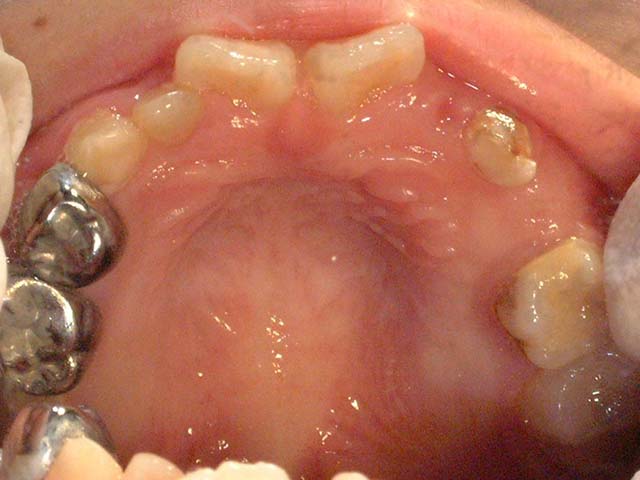

以下可以看到混合齒列期乳牙與恆牙在口內的對應位置

正常混合齒列